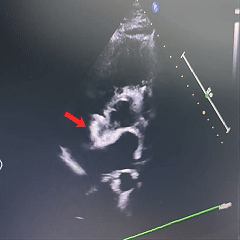

超声下确定封堵器左右两盘骑跨在房间隔两侧

超声下,封堵器结构稳定无散开,判断锁定成功

封堵器位置正确、夹持稳定、形态良好、无残余分流,封堵手术成功

沿房间隔可见封堵装置,沿其周围未测及残余分流。

超声提示:ASD封堵术后,无残余分流。

房间隔可见封堵器回声,位置固定,形态良好。房水平未见残余分流信号。

术后即刻超声检查显示封堵器位置正确、形态良好、夹持稳定,无残余分流。术后第1天和第2天的随访超声进一步显示房间隔可见封堵器回声,位置固定,形态良好,且房水平未见残余分流信号。